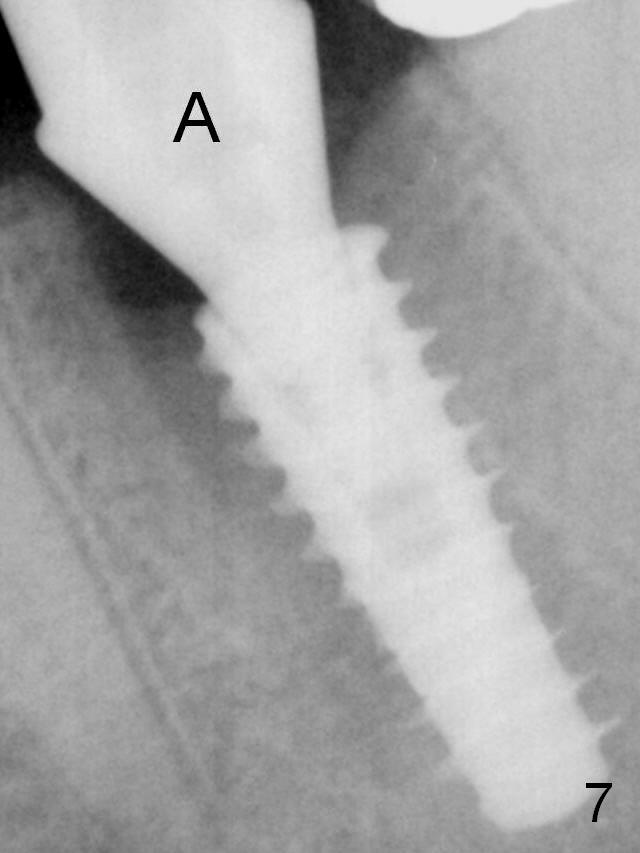

Insertion torque of a 5x13 mm implant is <20 Ncm (Fig.7). A 6.5x4(4) mm pair abutment is placed (A), apparently proper for restoration. Allograft is placed prior to immediate provisional. The patient complains of bad smell from the site 24 days postop. When the provisional is removed, the abutment is found to be mobile. When the latter is removed with local anesthesia, bone graft granules are attached to the socket above the lightly mobile implant. In fact the latter appears to be stable after a few turns by finger. A healing screw is placed; the socket is closed with collagen plug and 4-0 Chromic gut sutures. It appears that a larger implant should have been used to achieve higher torque. Two months later (3 months postop), the coronal end of the implant is partially exposed. A 5x4 mm healing abutment is placed. It appears that the implant is stable. The implant appears to have osteointegrated 4 months postop (Fig.11). Impression is taken. New bone has apparently covered the implant plateau 8 months postop (3 months post cementation (Fig.13 arrows)). The lower two-thirds of socket have disappeared.